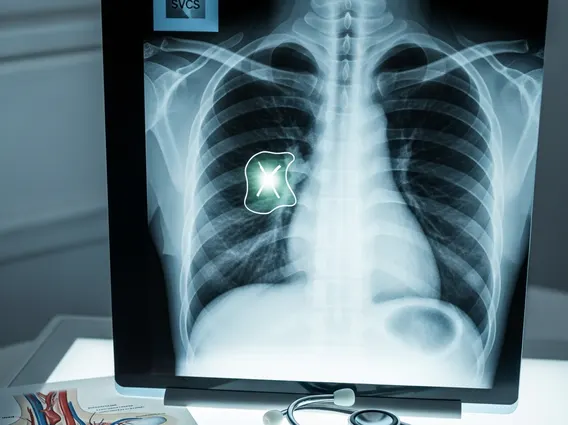

Effective **Superior Vena Cava Syndrome treatment** aims to alleviate symptoms and address the underlying cause of the obstruction. The immediate goals are to relieve discomfort and prevent life-threatening complications, while long-term treatment focuses on eradicating or controlling the primary disease.

Initial symptomatic management often includes elevation of the head of the bed, diuretics to reduce fluid retention, and corticosteroids to decrease inflammation and edema, especially when the obstruction is due to a tumor. Oxygen therapy may be provided for patients experiencing significant dyspnea. For definitive treatment, the approach depends heavily on the underlying cause:

- Anticoagulation: For cases caused by thrombosis, anticoagulant medications are used to prevent further clot formation and help dissolve existing clots.

- Surgery: Surgical intervention is rare but may be considered for benign causes or when other treatments have failed, involving bypass grafts or removal of the obstructing mass.

The choice of treatment is individualized, considering the patient’s overall health, the severity of symptoms, and the specific etiology of the syndrome. Close monitoring and follow-up are essential to assess treatment effectiveness and manage any potential complications.